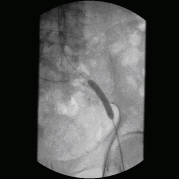

Abb. Stent